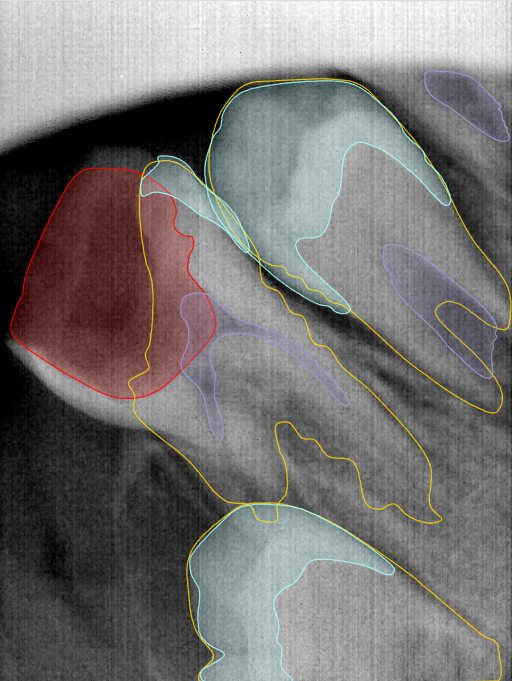

第二版算法问题测试

| 第一版 | 第二版 | 是否解决 | |

|---|---|---|---|

![]() | ![]() ![]() 边角识别有问题 龋齿识别不全 牙髓识别不全 | ![]() | 解决 |

![]() | ![]() 边角识别有问题 识别信息有误 自查(牙冠识别不全) | ![]() | 解决 |

![]() | ![]() ![]() 边角识别有误 大范围填充识别遗漏 | ![]() | 解决 |

![]() | ![]() 识别信息不全 | ![]() | 解决 |

![]() | ![]() ![]() 边角问题 牙胶识别不全 牙冠识别不全 | ![]() | 解决 |

![]() 换图片 | ![]() | ![]() 牙冠部分稍微白了一些就识别成小范围修补,部分判断异常 | 部分解决,修复类略敏感,牙冠部分稍微白了一些就识别成小范围修补,部分判断异常。 |

![]() | ![]() ![]() 牙冠识别不全 牙髓不全 根尖炎龋齿识别有误 | ![]() | 解决 |

![]() | ![]() | ![]() | 解决 |

![]() 换图片 | ![]() | ![]() | 解决 |

![]() | ![]() 牙冠识别有误 | ![]() | 解决 |

![]() 换图片 | ![]() ![]() 边角识别有误 | ![]() 修复类敏感 | 部分解决,图像过白,导致修复类判断异常。 |

![]() 换图片 | ![]() 牙冠识别不全 | ![]() 修复类敏感 | 部分解决,图像过白,导致修复类判断异常 |

结论:修复类出现了不鲁棒的情况,后续需要加入轮廓的扩充数据进行增强。